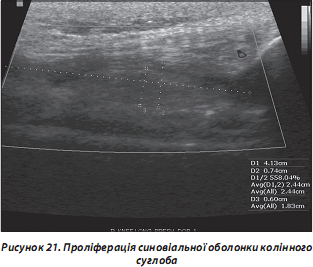

б) гіпертрофія синовіальної оболонки (рис. 21);